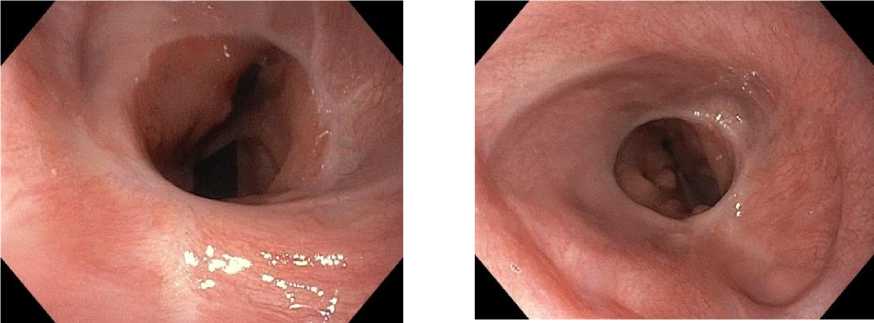

Рис. 2. ЭФГДС до начала лечения. Тип III по Borrmann

Fig. 2. Pre-treatment esophagogastroduodenoscopy (EGD). Borrmann Type III

Рис. 10. ФГДС после 6 курсов лечения и выполненной гастрэктомии: 40 недель динамического наблюдения. Эзофагоэнтероанастомоз проходит свободно, слизистая без признаков воспаления

Fig. 10. EGD after 6 treatment cycles and gastrectomy. 40 weeks of follow-up. Patent esophagoenteroanastomosis, no signs of mucosal inflammation